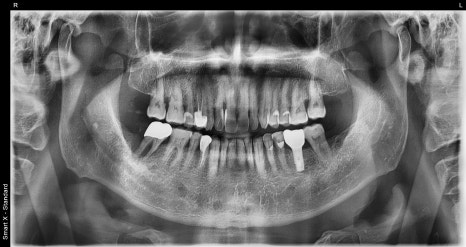

왼쪽은 초진 당시 촬영한 파노라마 엑스레이, 오른쪽은 환자분의 구강 내 사진입니다.

오른쪽 아래 어금니(#47)는 엑스레이에서 잇몸뼈가 많이 녹아 있었고 치아도 많이 흔들려, 전체 잇몸치료와 함께 #47 발치 & 임플란트 치료를 계획하고 있었습니다.